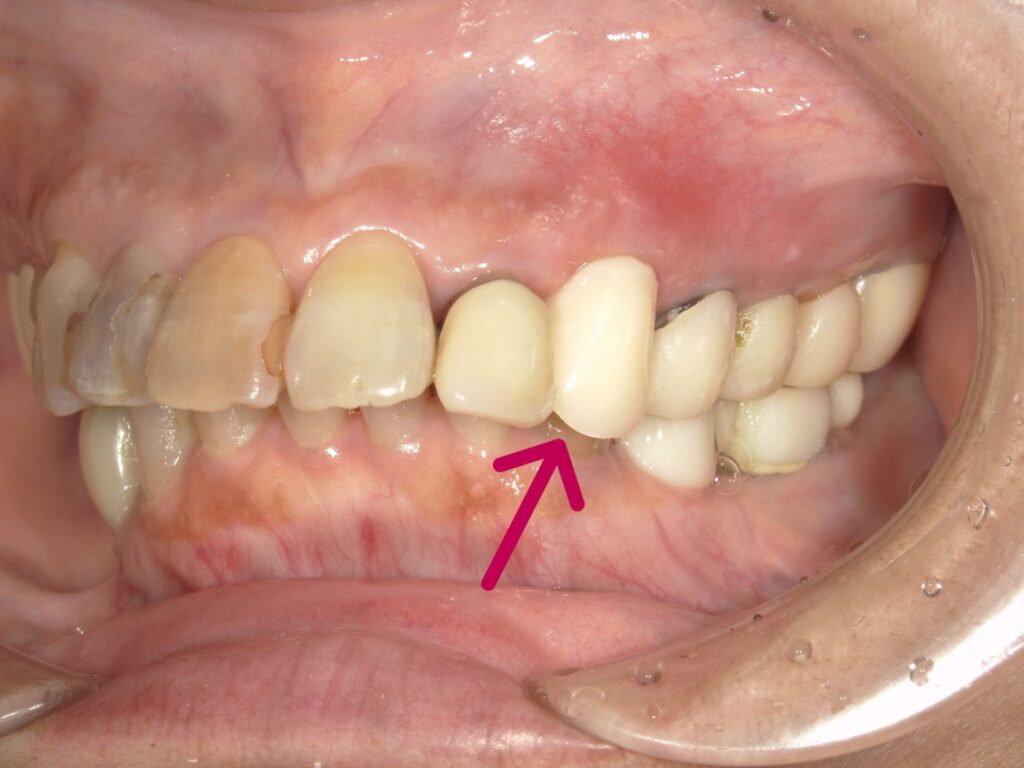

【仮歯をセットしました】

左上3歯根破折のため抜歯。

抜歯と同時にインプラント埋入。その日のうちに仮歯まで装着します。切開縫合を行わないため腫脹、痛みの少ない患者さんにやさしい術式になります。

左上3歯根破折。右下56は当院にてインプラント埋入

抜歯と同時にインプラント埋入。サージカルガイドを使用することにより正確な位置に埋入可能